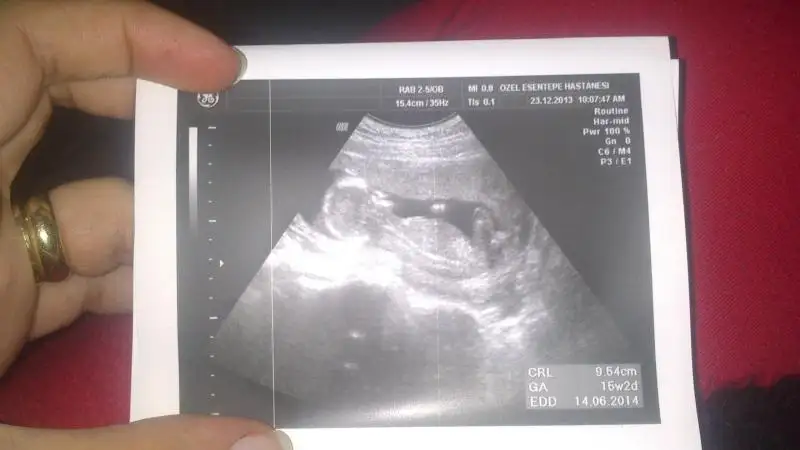

Ayni bu goruntu benim suanki kizimin ultrasonuna benziyor canim bendede bu haftada kesin erkek demusti sonrada kiz dedi Bence senin bebis de kiz olucak kesin haber ver sonucunu

Benim ultrasonla ayni yeni koydugun kizin olucak insallh